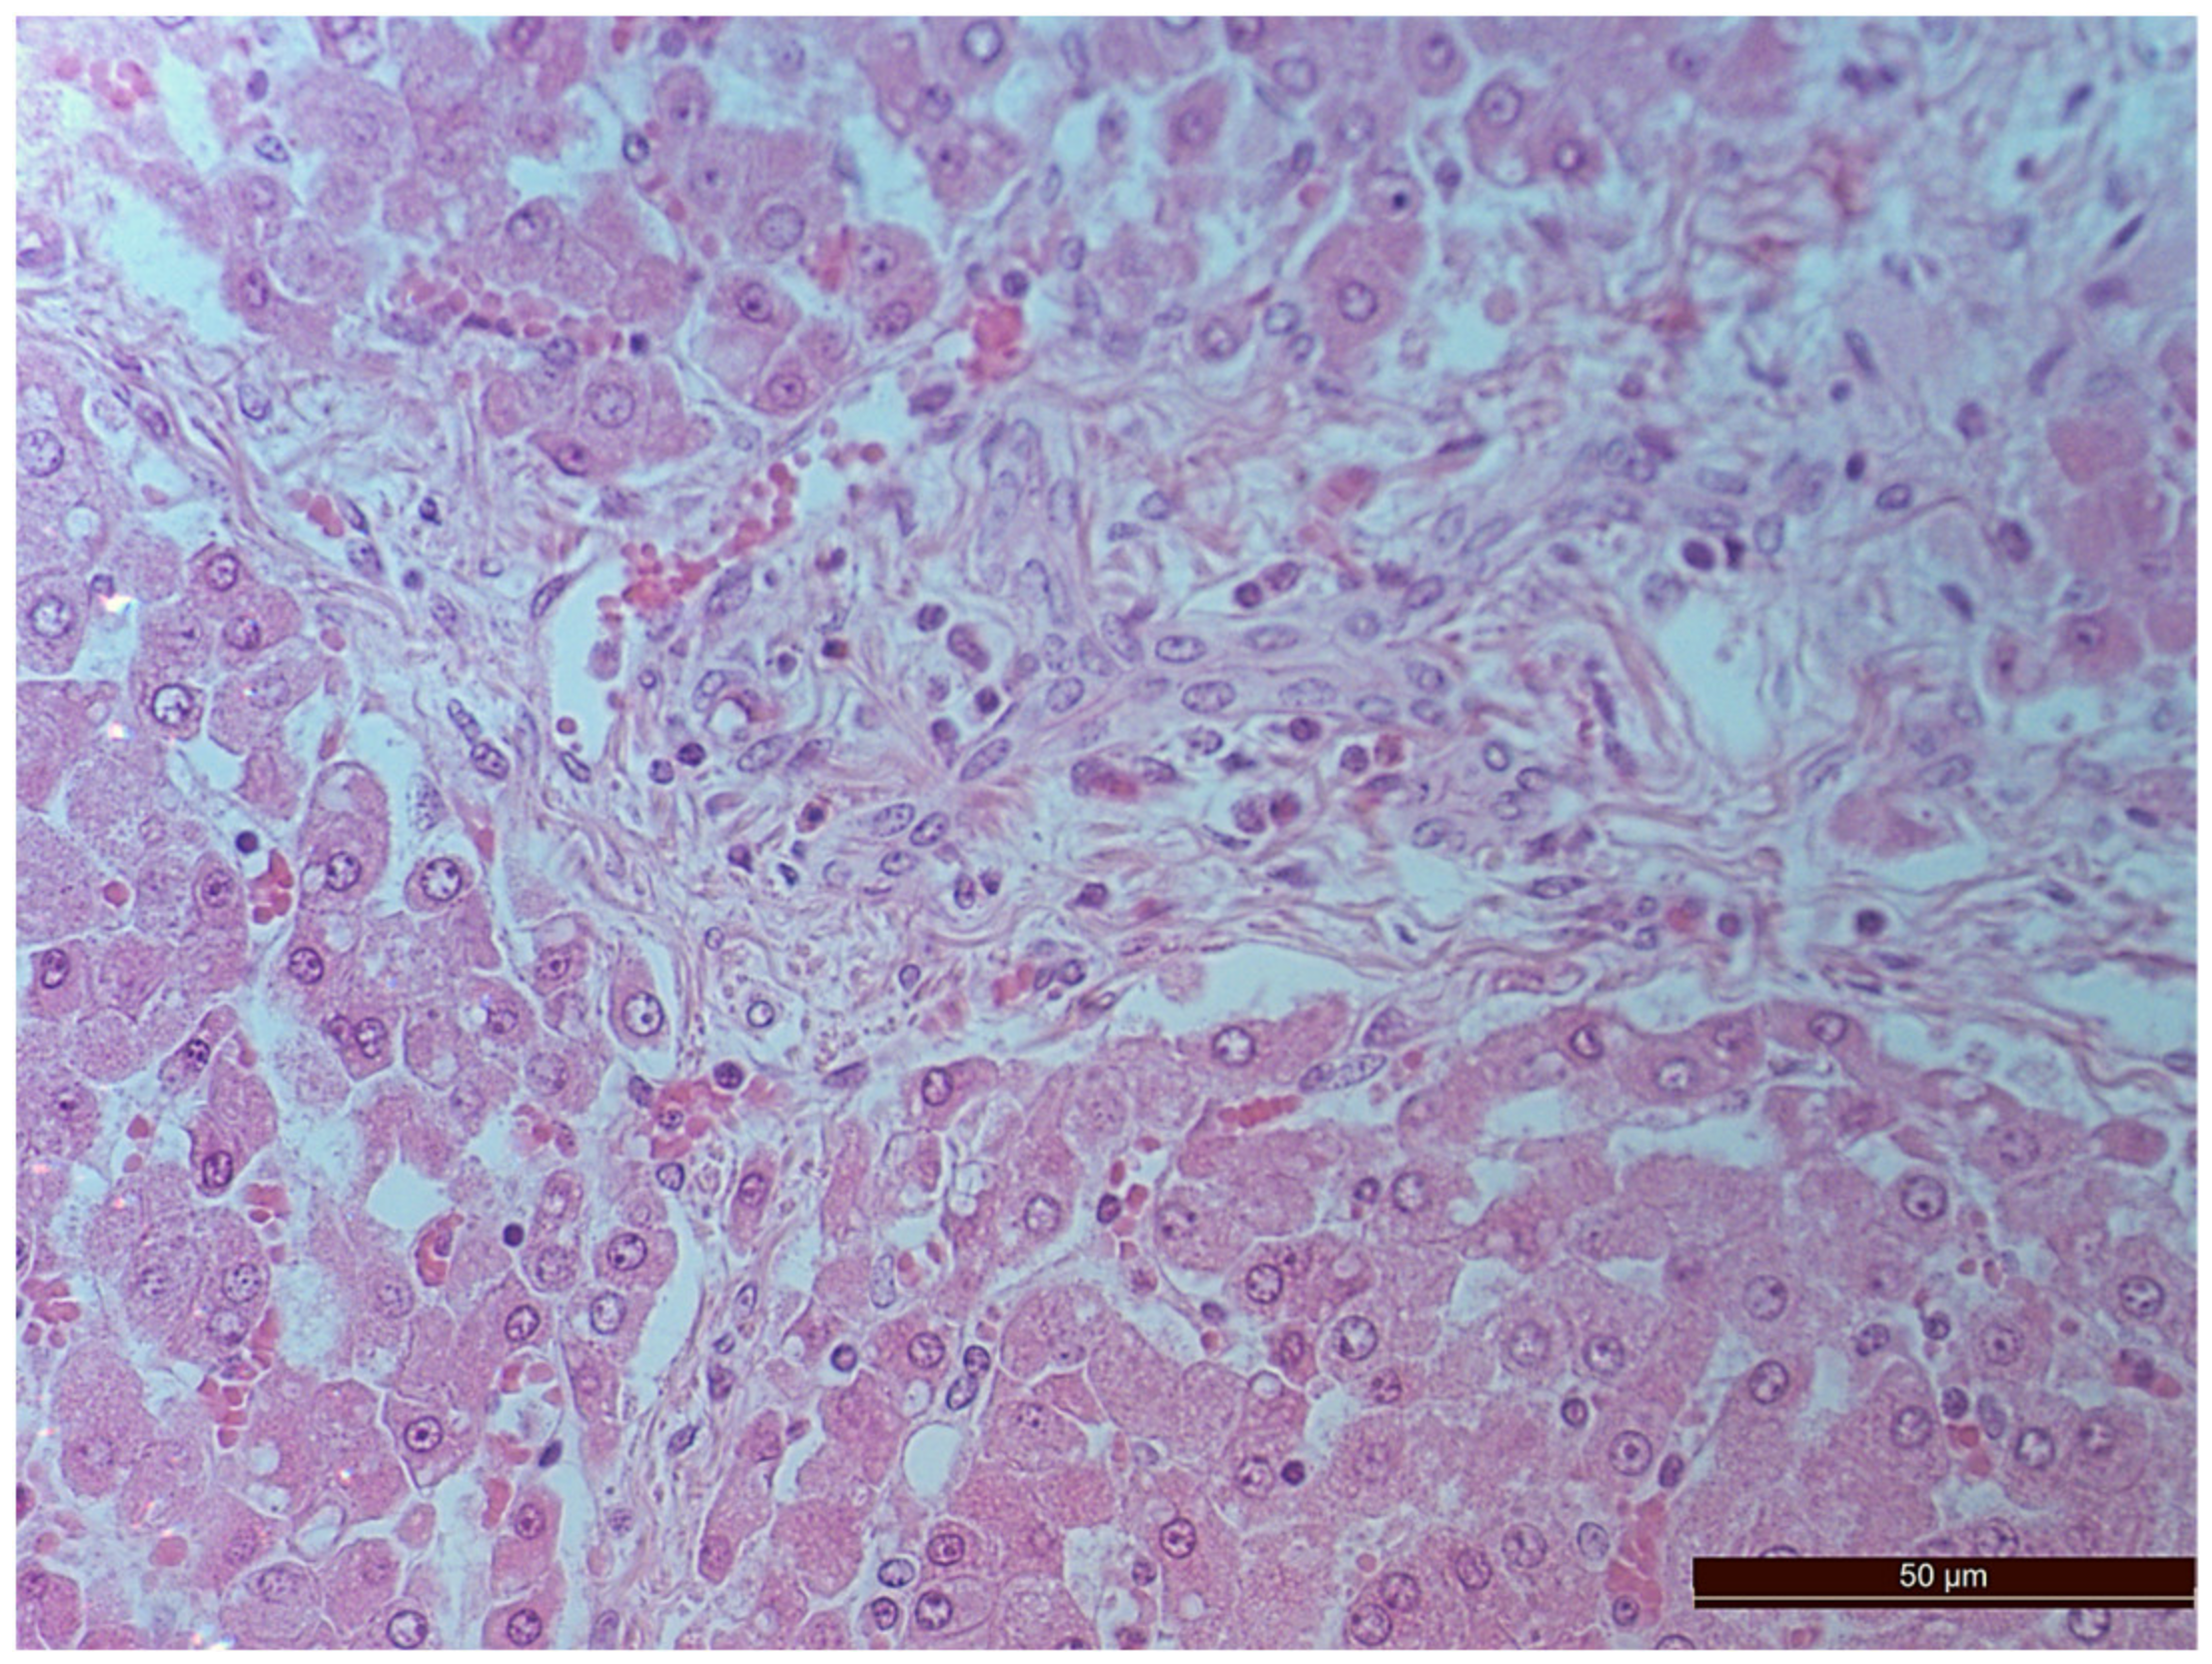

3.2. Pathology of the Liver